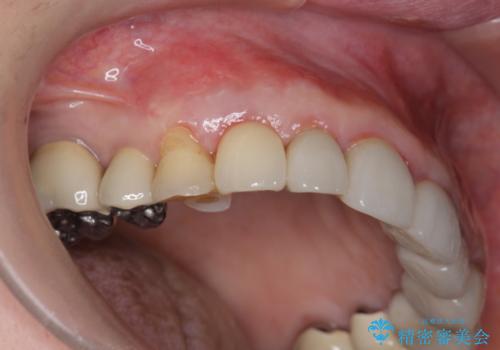

クラウン下に再発した深い虫歯 インプラントによる機能回復

- 定期検診で通院されていたところ、20年前に他院で治療した前歯のセラミック歯の下に深い虫歯が再発していることがわかりました。

ブリッジや歯の挺出を行い保存する提案も行いましたが、短期間の定期的な通院が難しくインプラントによる少ない回数での治療を希望されました。